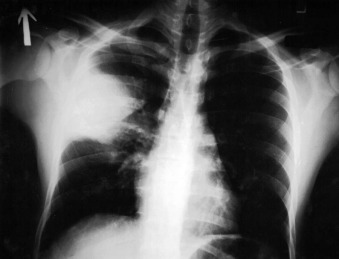

Previous Image Next Image 3-s2.0-B9781455748013002319-f231-007-9781455748013 Plague effect on the lungs